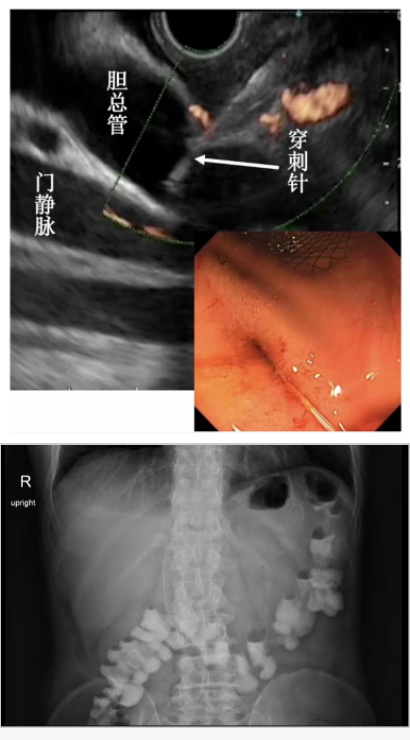

对于子宫癌腹腔转移导致十二指肠及胆道梗阻患者,将内镜与超声内镜结合,同步实施十二指肠支架和胆道支架放置术,让病人经口吃饭,最大限度地维持患者的生活质量。